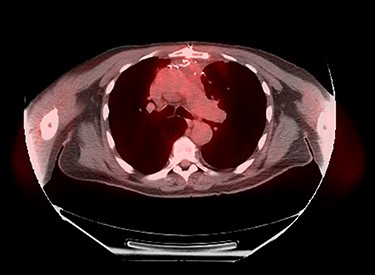

Sixty-three-year-old male was with the history of diabetes and hypertension who presented with 2 days of new onset, intermittent and non-pleuritic left-sided chest pain, with a few months of new onset exertional dyspnea. Chest X-ray showed a convex shaped mass at the left hilum. Chest CT angiography revealed a 5.6 × 7.1 × 5.4 cm hypodense mass in the anterior mediastinum involving the adjacent anterior medial left upper lobe, and adjacent mildly enlarged aorticopulmonary window lymph nodes (Fig. 1). PET scan demonstrated a hypermetabolic anterior mediastinal mass adjacent to medial left upper lobe highly suggestive of malignancy (Fig. 2). Ultrasound-guided core needle biopsy showed nests of small cells with peripheral palisading and focal abrupt transition to squamous cell, consistent with basaloid carcinoma of thymic gland. Immunostainings of the tumor cells were positive for cytokeratin AE1/AE3, cytokeratin CK904, p63 and p40.

Pre-operative PET scan demonstrating a hypermetabolic anterior mediastinal mass.